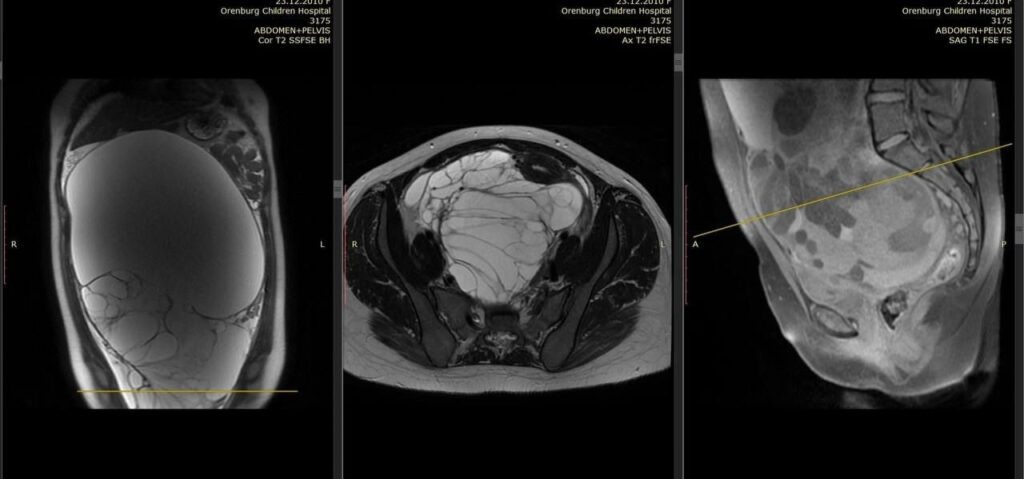

13-летняя девочка пожаловалась на боли и увеличение живота. Врачи областной детской клинической больницы обнаружили у пациентки гигантское образование, которое занимало всю брюшную полость. Оперативное вмешательство было осложнено плохим состоянием одной из почек, пострадавшей от сдавления. Тем не менее хирурги смогли полностью удалить опухоль – гигантскую муцинозную цистаденому яичника. В операционную бригаду ОДКБ вошли хирург – врач акушер-гинеколог детского отделения №1 Аниса Хусаинова, ассистент – завотделением хирургии №1 Андрей Баканов, анестезиолог-реаниматолог Элеонора Рыхлова, операционная сестра Татьяна Демида. Фото: ОДКБ

13-летняя девочка пожаловалась на боли и увеличение живота. Врачи областной детской клинической больницы обнаружили у пациентки гигантское образование, которое занимало всю брюшную полость.

Оперативное вмешательство было осложнено плохим состоянием одной из почек, пострадавшей от сдавления. Тем не менее хирурги смогли полностью удалить опухоль – гигантскую муцинозную цистаденому яичника.

В операционную бригаду ОДКБ вошли хирург – врач акушер-гинеколог детского отделения №1 Аниса Хусаинова, ассистент – завотделением хирургии №1 Андрей Баканов, анестезиолог-реаниматолог Элеонора Рыхлова, операционная сестра Татьяна Демида.